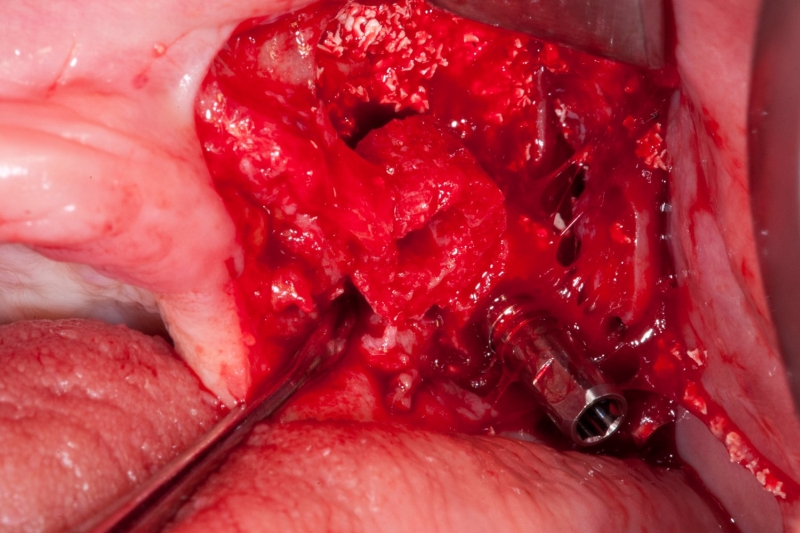

03/18 - Simultaneous horizontal augmentation

Vertical augmentation & sinus lift with maxgraft® bonering - Dr. O. Yüksel and Dr. B. Giesenhagen